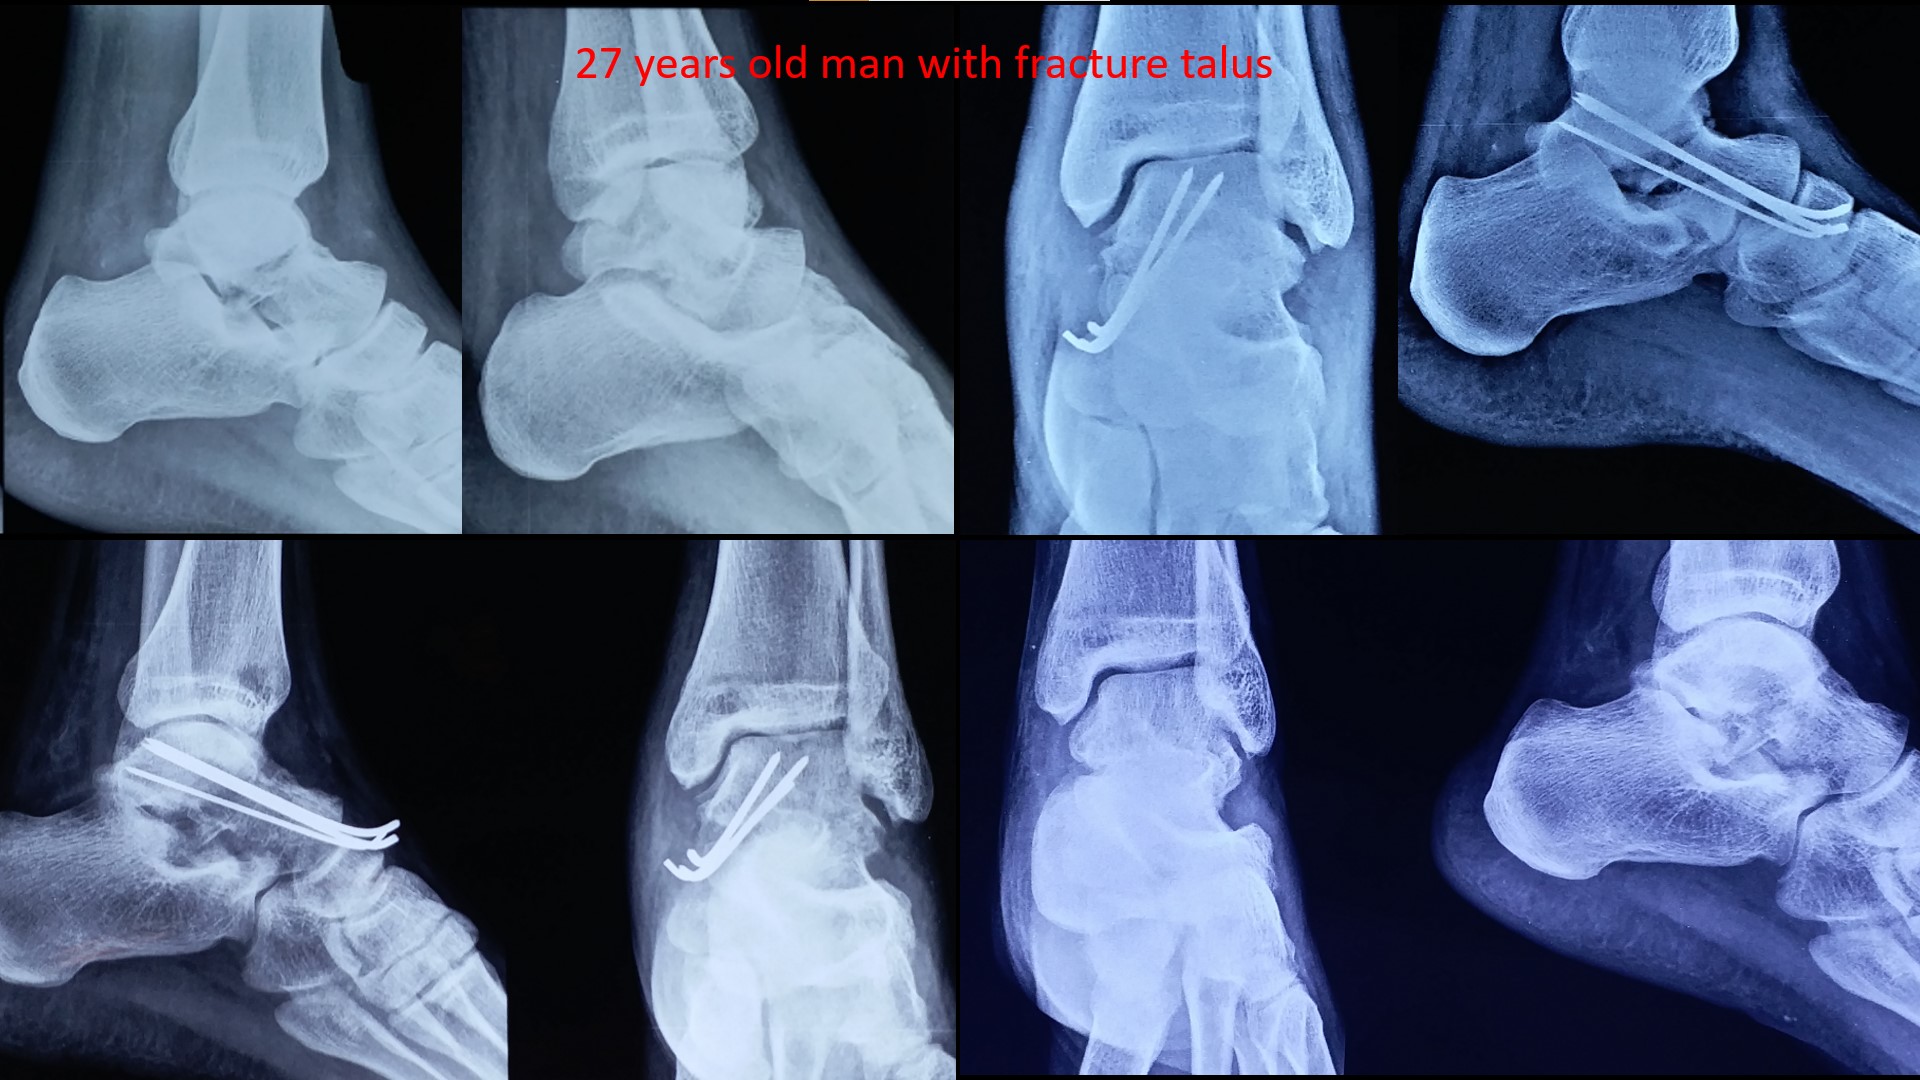

Talus